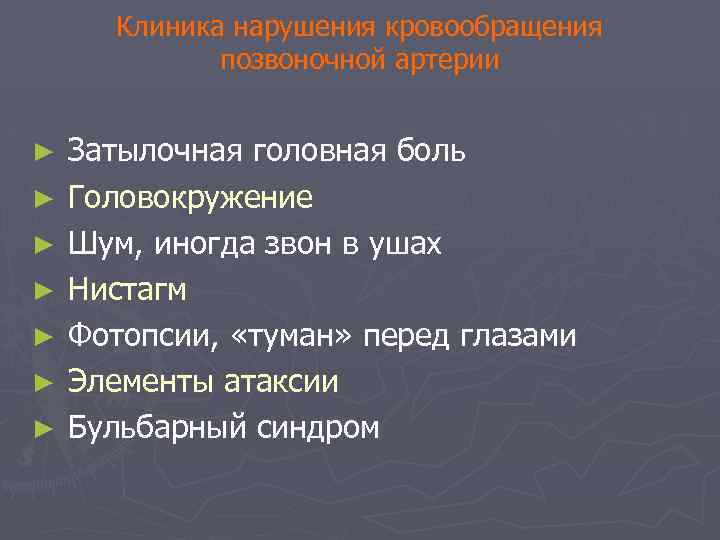

Клиника нарушения кровообращения позвоночной артерии ► ► ► ► Затылочная головная боль Головокружение Шум, иногда звон в ушах Нистагм Фотопсии, «туман» перед глазами Элементы атаксии Бульбарный синдром